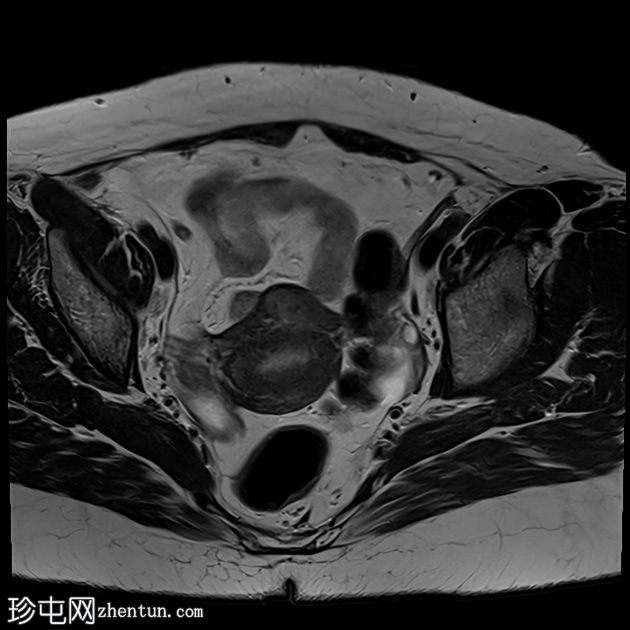

T2加权像

轴位T2加权像

脂肪抑制像

可见膀胱左侧壁有一边界清晰的T2低信号实

性病

灶,无扩散受限,均匀强化。未见膀胱周围侵犯或肾积水。

子宫底部前壁可见一小肌瘤。双侧卵巢可见无强化囊肿。盆腔及腹股沟未见异常淋巴结肿大。

这是一例经组织学证实的膀胱平滑肌瘤病例。